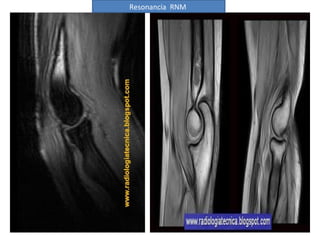

Resonancia RNM